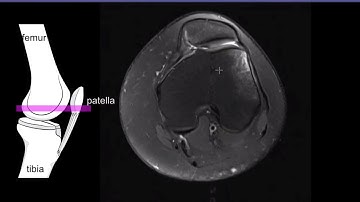

Patellar Instability - What and How to Measure